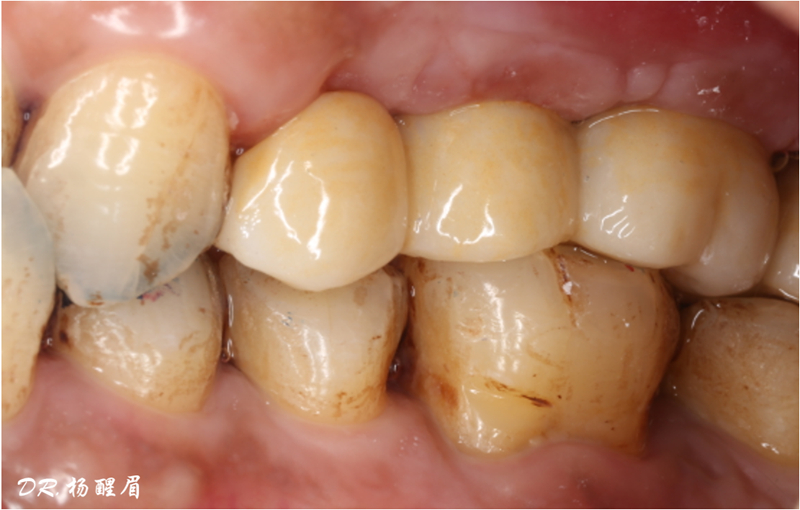

修復完成

®多顆植體位點及角度的精確性,確保后期修復方案順利完成,也使患者能在使用過程中承受最佳的咬合力